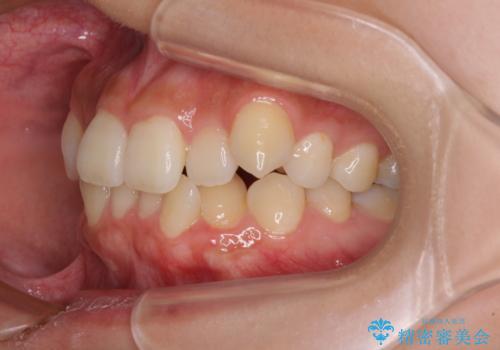

デコボコと八重歯の目立つ前歯 ワイヤー装置による抜歯矯正

- 上下前歯のデコボコと八重歯を気にして来院された患者様です。

叢生を解消する際に出っ歯とならないようにするために、上下左右の小臼歯計4本を抜歯することとしました。